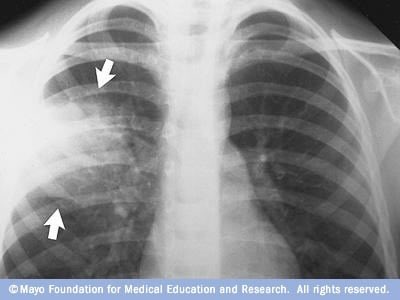

diagnosed through a physical examination, chest x-ray, and blood tests. A chest x-ray can show inflammation and fluid in the lungs, while blood tests can help identify the type of pathogen causing the infection. In some cases, other tests such as a sputum culture or bronchoscopy.